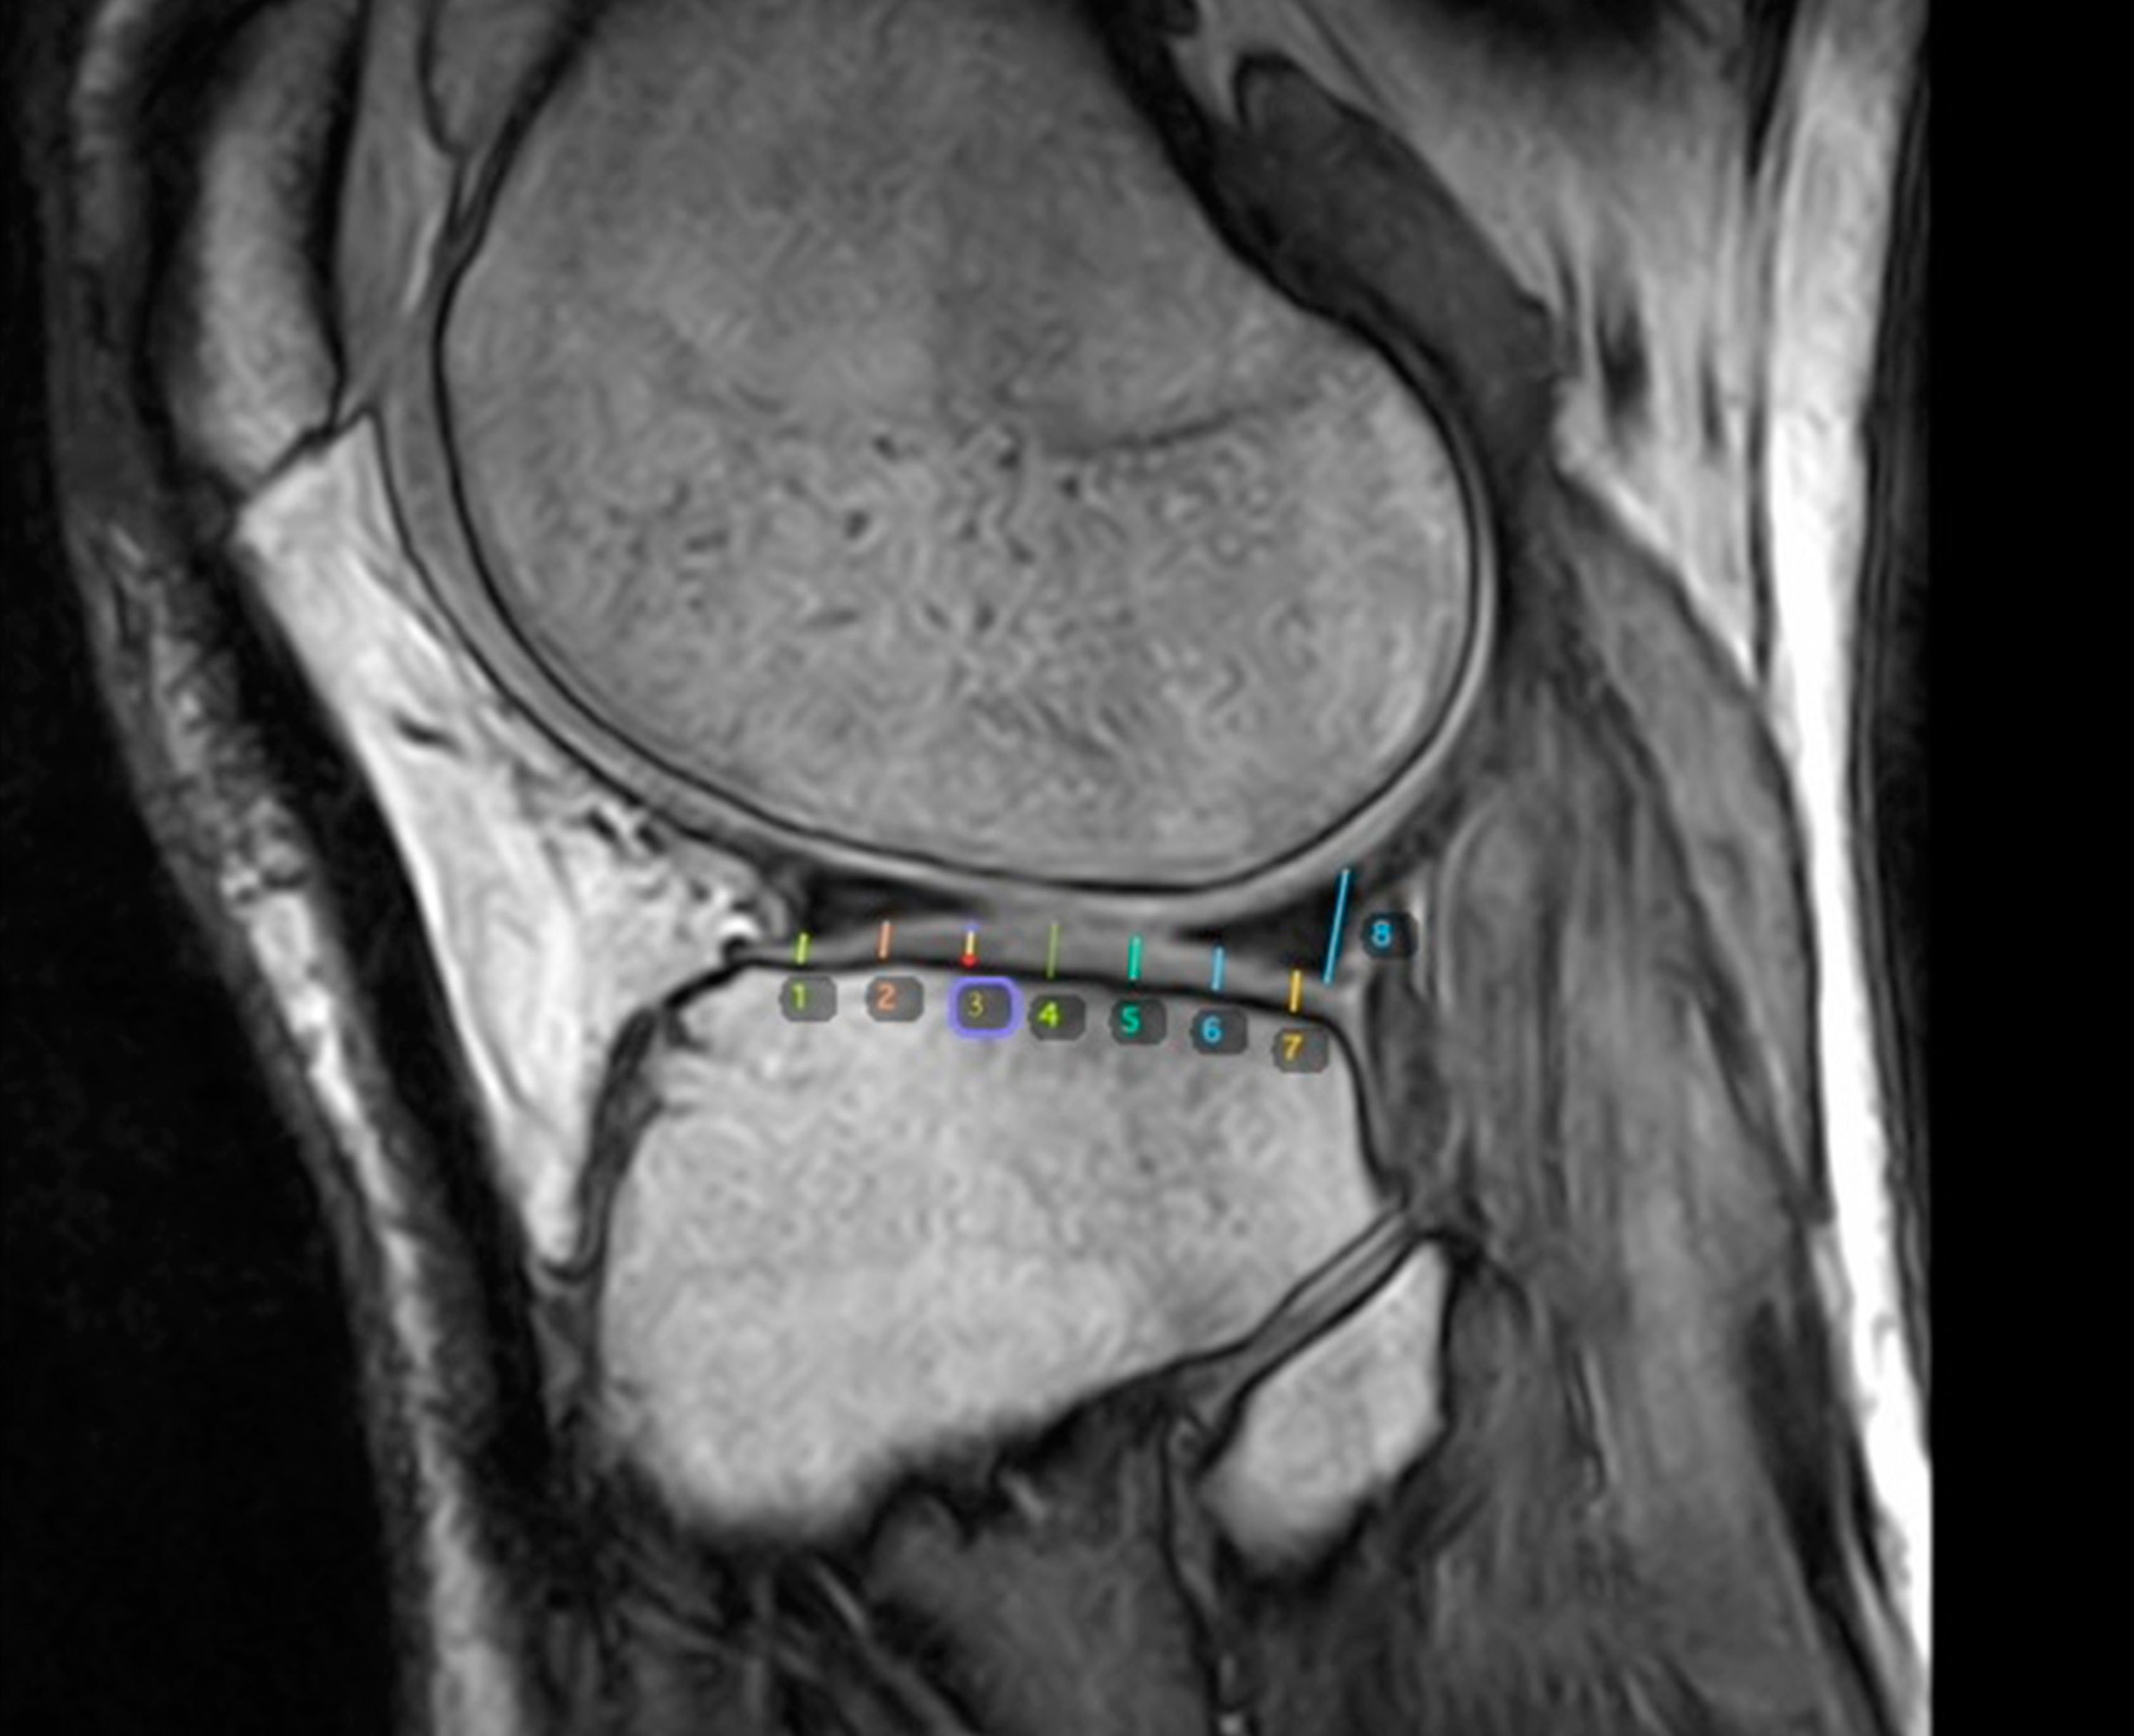

2.5. Evaluation of Knee Cartilage Thickness Using MRI

2.6. Medial and Lateral Femoral Condyle

2.7. Medial and Lateral Tibial Condyle